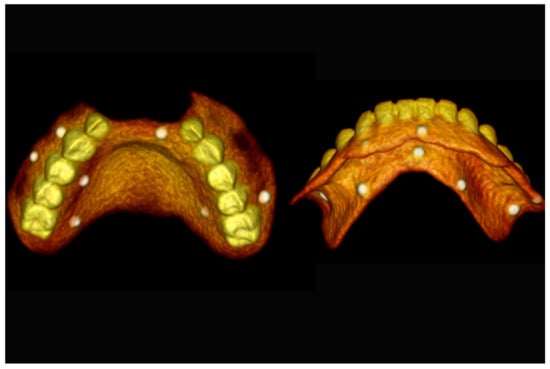

Figure 16.

Three-dimensional (3D) CBCT scan images with the patient wearing the planned prosthesis.

Figure 17.

Three-dimensional (3D) CBCT scan images of the prosthesis equipped with integrated radiopaque reference spheres scanned separately.

The number, the length, the diameter and the placement of computational virtual implants were determined with respect to the design of the final prosthesis the available residual bone volume and the anatomical limitations according to the previously described technical procedure (Figure 16, Figure 17, Figure 18, Figure 19, Figure 20 and Figure 21).